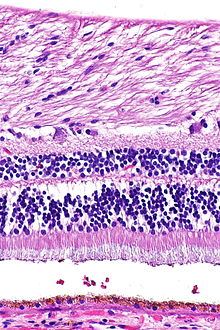

Ein Netzhautquerschnitt zeigt im Lichtmikroskop eine auffällige Schichtung, die durch abwechselnd zellkernreiche und -arme Lagen gebildet wird. Die Schichten besitzen charakteristische Zelltypen und subzelluläre Kompartimente. Die Nervenzellen der Netzhaut lassen sich in drei Gruppen gliedern:

Schichten der Netzhaut

Das durch die Pupille einfallende Licht durchdringt Linse und Glaskörper als transparente Medien und passiert dann mehrere Schichten der Netzhaut, bevor es von den Photorezeptorzellen des Neuroepithels detektiert wird, die dem außen anliegenden Pigmentepithel zugewandt sind. Vom Glaskörper her zur Aderhaut hin, also bezogen auf das Auge von innen nach außen, zeigt die lichtempfindliche Netzhaut einen schichtartigen Aufbau aus Zellkörpern im Wechsel mit Zellfortsätzen. Hierbei lassen sich meist zehn Schichten unterscheiden, im Bereich der Sehgrube des Gelben Flecks sind einige seitwärts verlagert.